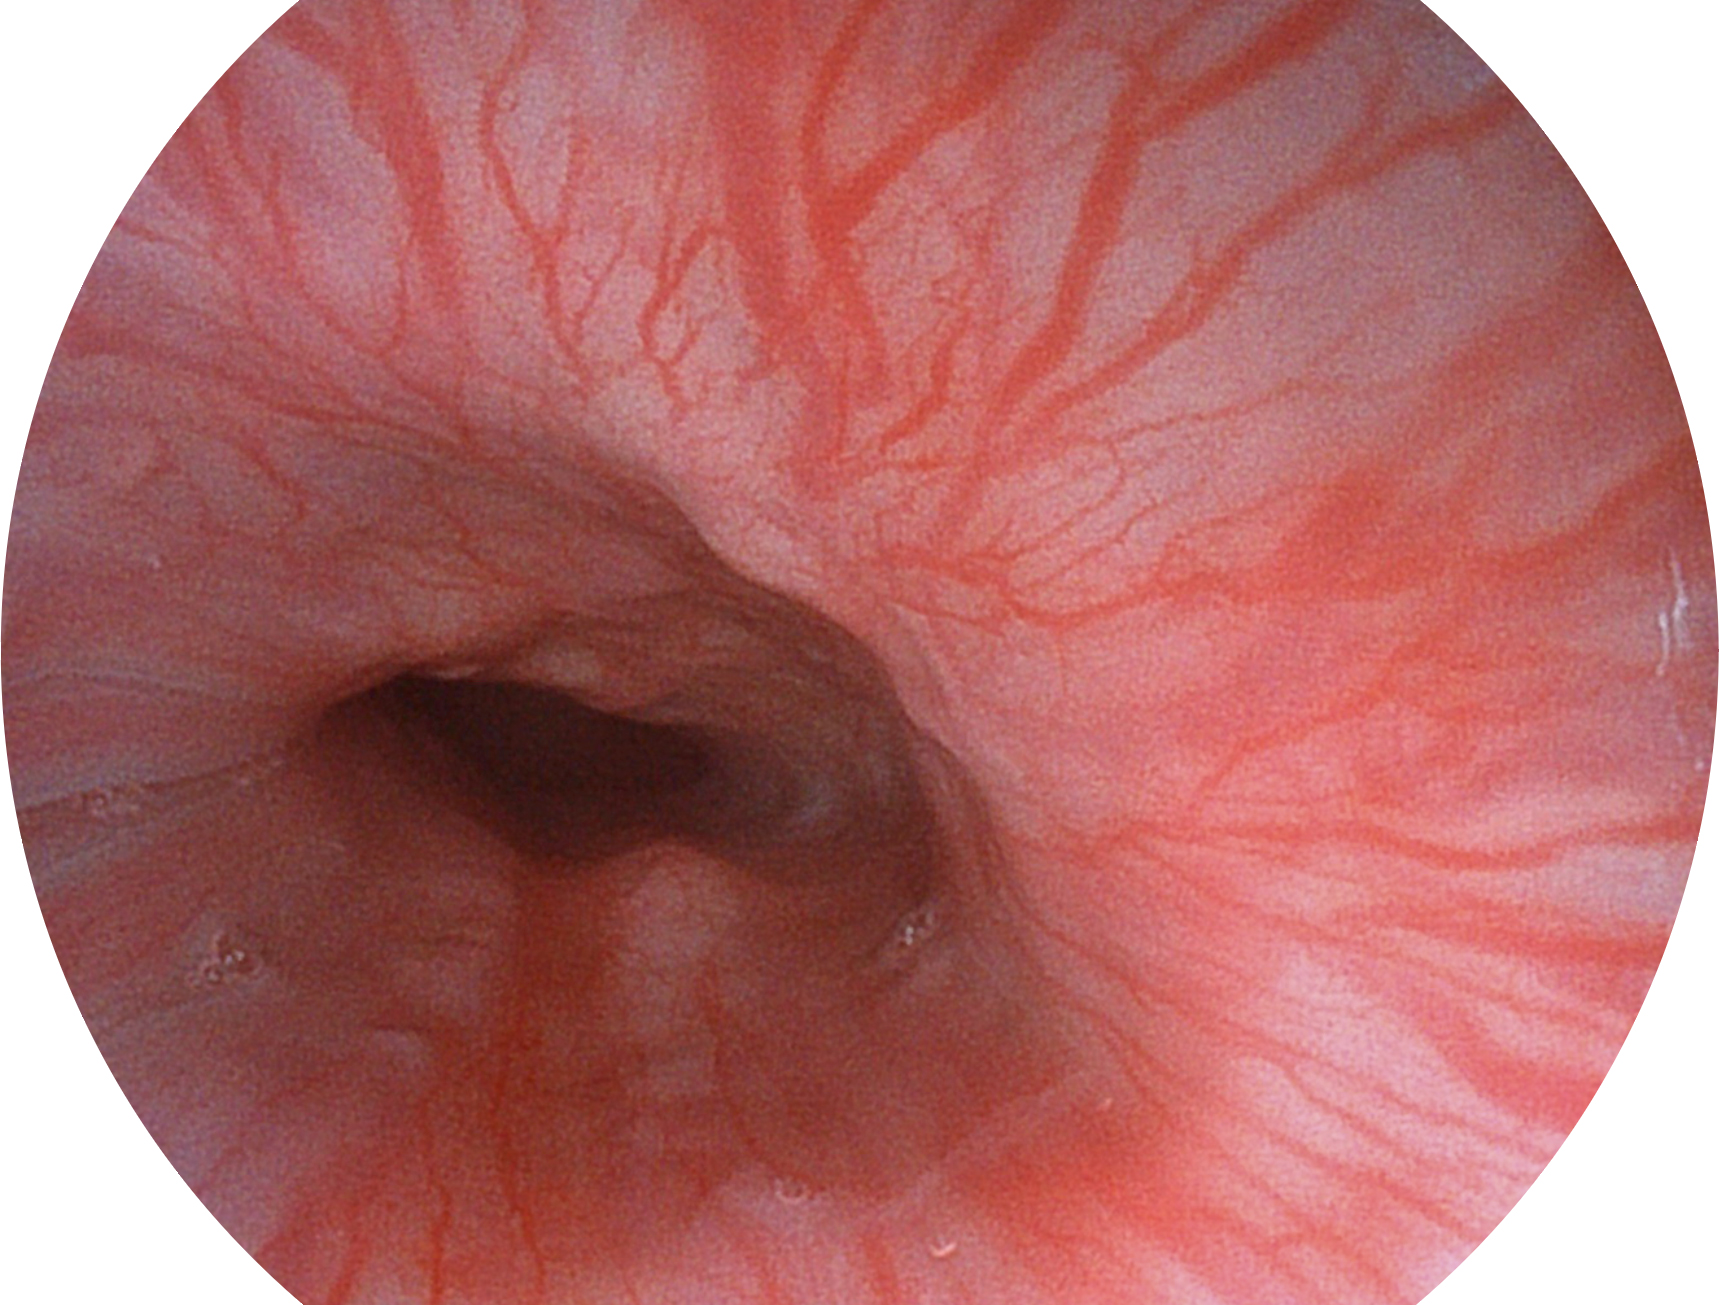

1xBET新开发的内镜染色技术,主要是基于多波长LED 光源的开发,VLS-55Q 四波长LED 光源是由四个不同颜色的LED光按照相应照明模式所规定的特定发光比例进行合束后形成,合束后形成的照明光的光谱由红光、绿光、蓝光及蓝紫光这四个不同的波段范围构成。具有更高光谱自由度,通过光谱比例的控制,实现了聚谱成像技术,英文全称为“Spectral Focused Imaging, SFI”,缩写为“SFI”和光电复合染色成像技术,英文全称为“Versatile Intelligent Staining Technology, VIST”,缩写为“VIST”。